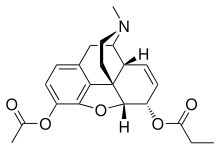

- Diacetyldihydromorphine (dihydroheroin, acetylmorphinol)

3,6-Dibutanoylmorphine |  Diacetyldihydromorphine Diacetyldihydromorphine(dihydroheroin, acetylmorphinol) | ||